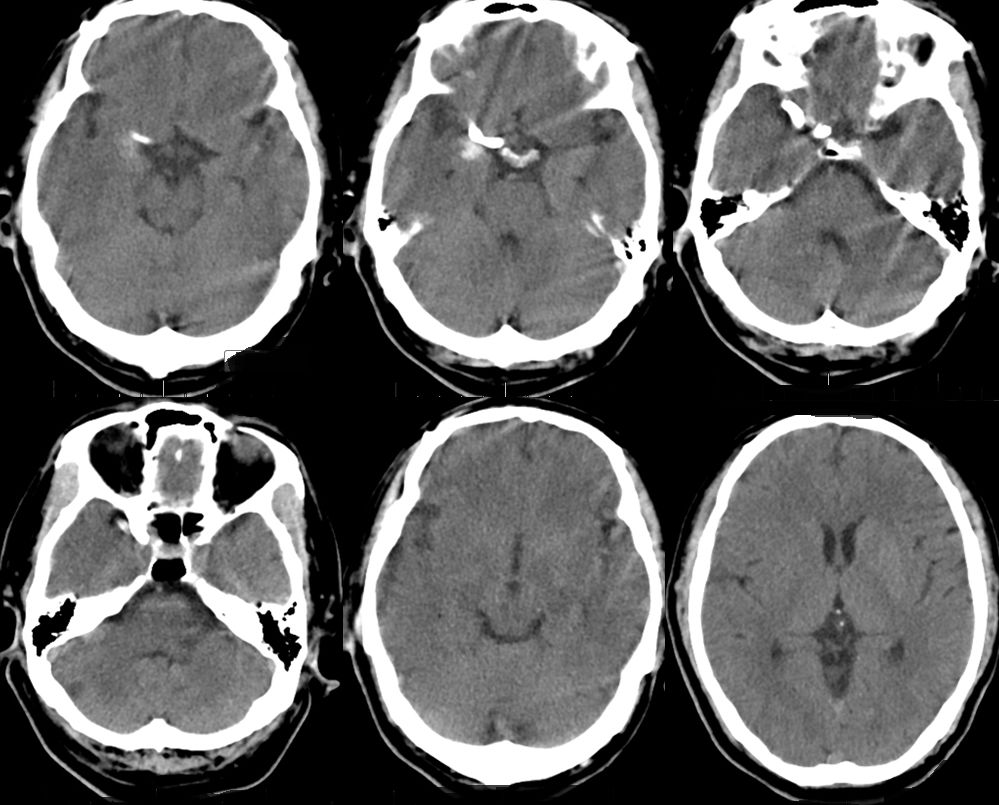

1、术后18小时CT(图五)。

术后3天CT(图八)。